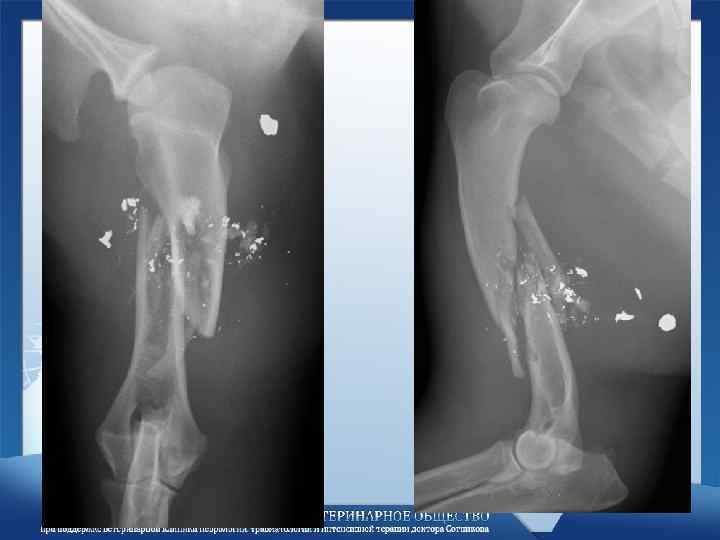

Интрамедулярный остеосинтез • Оскольчатые переломы - прямое противопоказание! • Просто, не всегда правильно! Интрамедулярный остеосинтез • Оскольчатые переломы - прямое противопоказание! • Просто, не всегда правильно!

Не надо так делать! Не надо так делать!